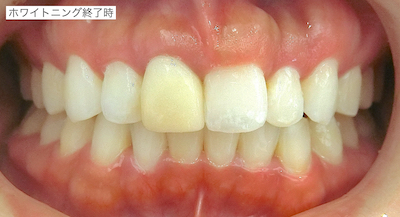

比較です。

旧仮歯を撤去したところ、歯根が一部水平的に破折していました。歯肉のラインが歪になっていたのはこのことが原因であったと説明しました。支台築造を行い、仮歯を作成しました。患者さんはホワイトニングを希望しておられたので、ホームホワイトニングを行ったのちに周りの歯の色に合わせてセラミック冠を作成することで同意頂いたので、ホームホワイトニングを行いました。

初診時との比較です。